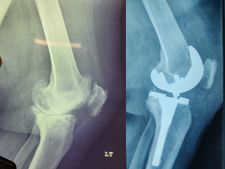

62 year old female with stage 4 OA

Primary Left TKR

Pre-op images of Right Knee

Post op images of Right knee